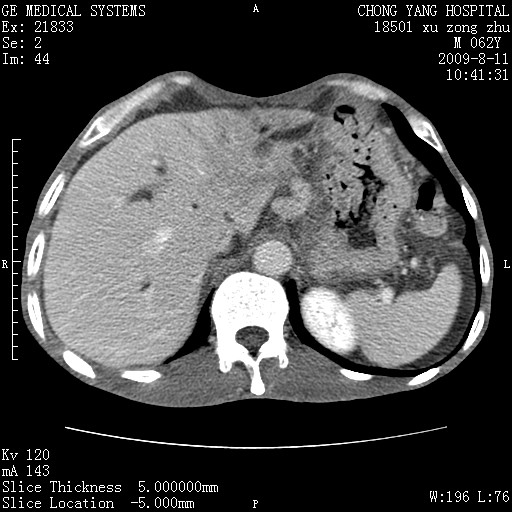

以下是引用杀毒软件在2009-8-11 16:35:00的发言:[br]肝内胆管扩张局限于左叶,胆管内有结石伴肝外胆管结石,胆管壁增厚呈弥漫性并发腹腔积液,胰腺边界模糊。[br][br]考虑---胆总管及肝内胆管结石继发胆管炎及胰腺炎,左肾下极囊肿,腹水。

以下是引用zjzjr在2009-8-11 17:35:00的发言:[br]肝内胆管扩张局限于左叶,胆管内有结石伴肝外胆管结石,胆管壁增厚呈弥漫性并发腹腔积液。[br][br]考虑---胆总管及肝内胆管结石继发胆管炎,左肾下极囊肿,腹水。